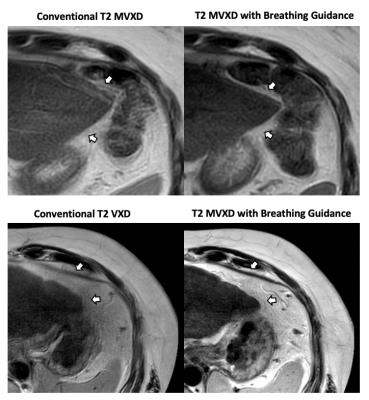

Representative images of two patients who underwent liver MRI with T2conv followed by T2BG. T2BG provides high image quality with significant improvement of sharpness and reduction of breathing artefacts during shorter scan time